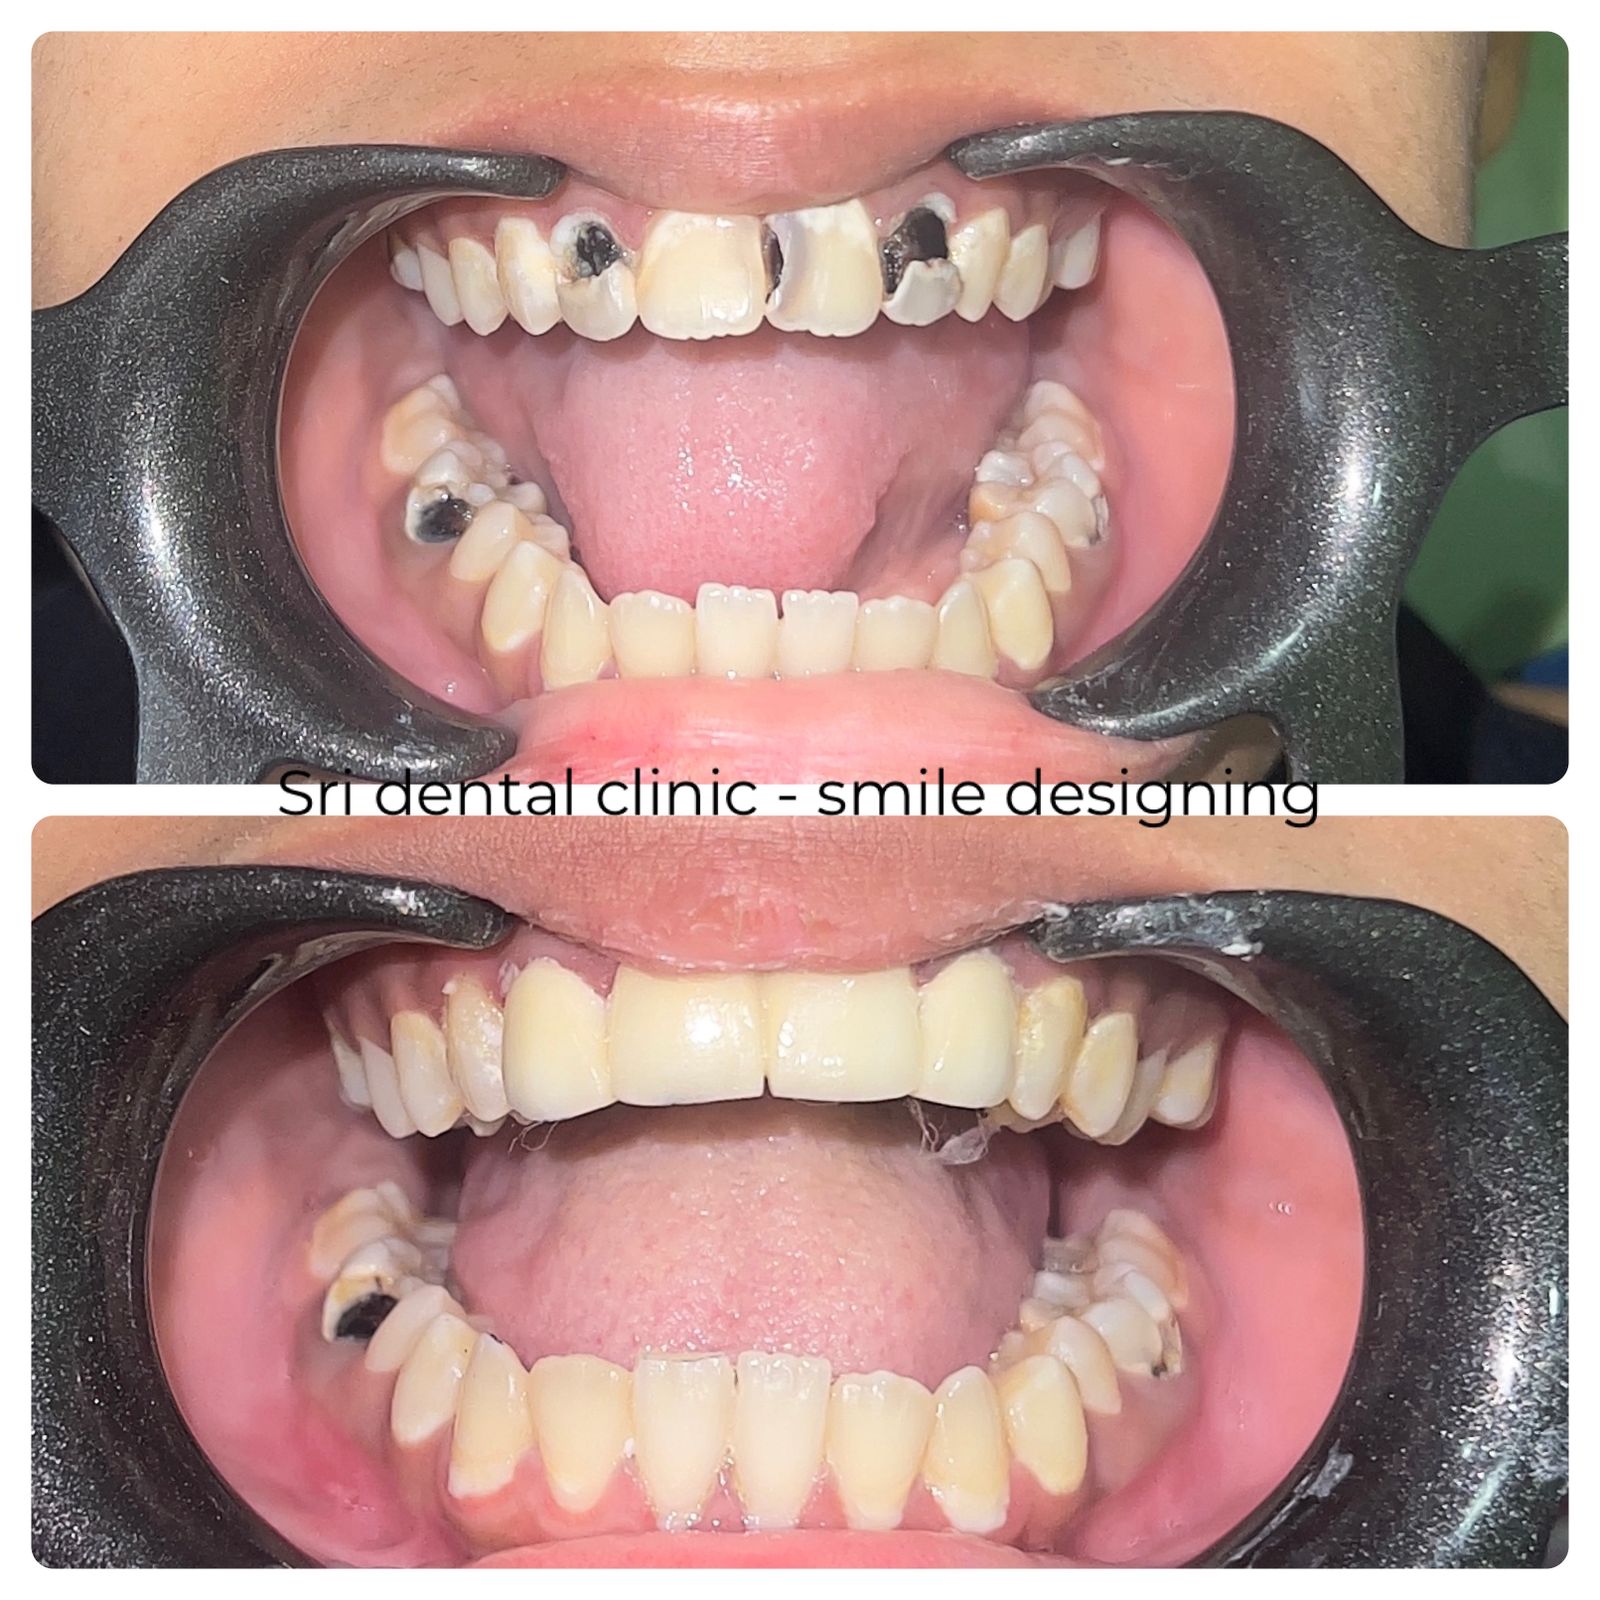

Dental Prosthetics restore lost or damaged teeth to improve oral function, aesthetics, and overall dental health.

Types of Dental Prosthetics We Offer

Crowns

A crown is a tooth-shaped cap placed over a weak or root-canal-treated tooth to restore its shape, strength, and appearance.

Bridges

Bridges fill the space created by one or more missing teeth, using adjacent teeth as support.